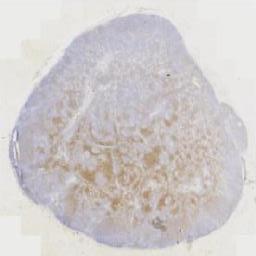

免疫组化: 阳性表达:S100、CD68、CyclinD1、Lambda、Kappa。MUM1.阴性表达:CD34、SMA、ALK(5A4)、CD1a。其他:Ki67(+,约5%),P53(+,野生型)。